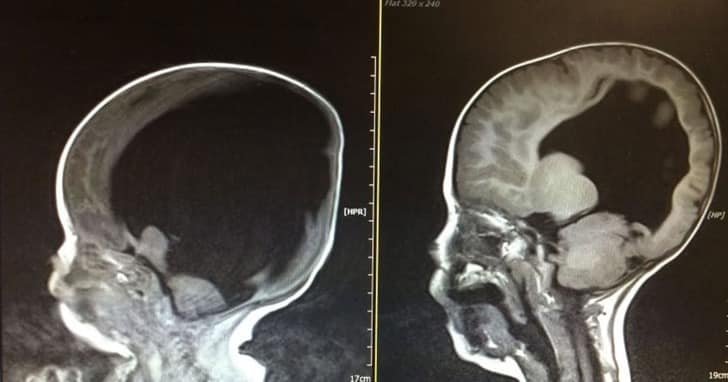

O pequeno tinha hidrocefalia e, como consequência, não somente sua cabeça era muito grande, mastambém quase não possuía cérebro: tinha somente 2%.

Aos quatro anos, os doutores quiseram checar sua condição e o que viram nas radiografias era simplesmente incrível. Noah não era um “milagre” somente por sobreviver… era porque seu cérebro começou a crescer e desenvolver-se.

Noah é um menino realmente feliz. Utiliza uma cadeira de rodas para movimentar-se, canta, fala e nunca deixa de sorrir. Seu cérebro já tem 80% de seu tamanho normal.